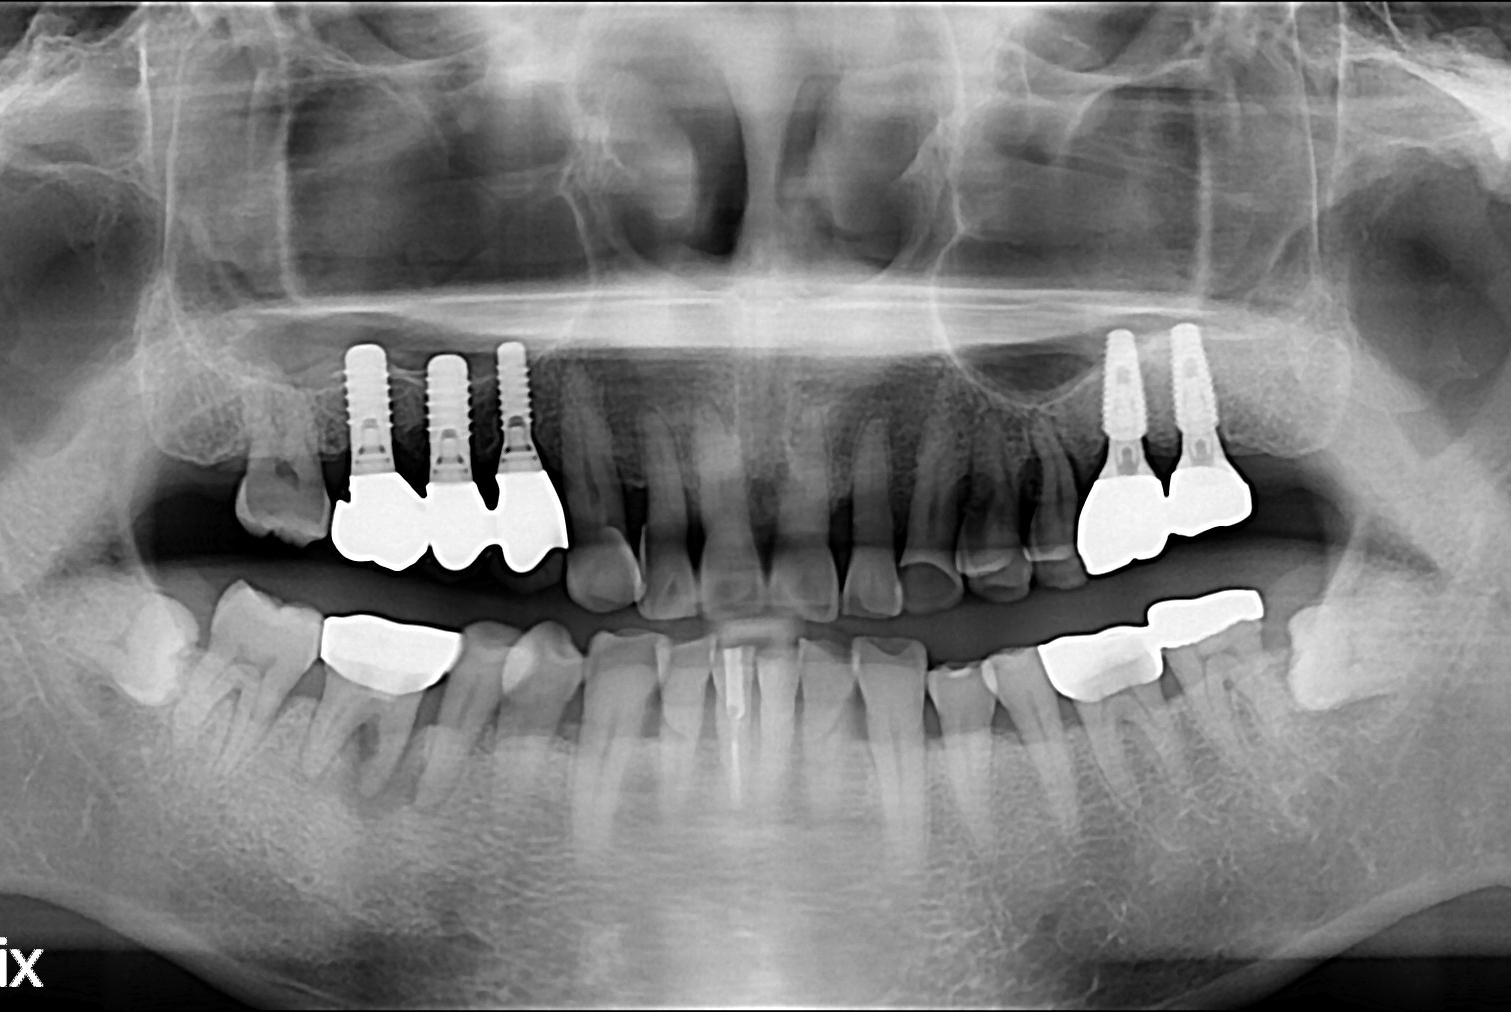

치료전 : 2018-05-09

치료후 : 2018-06-22

세종치과는 많은 환자와 다양한 케이스를 바탕으로 항상 편안한 임플란트 수술을 제공하고자 노력하고,

오래동안 튼튼히 쓸 수 있는 임플란트 수술을 가장 큰 목표로 삼고 있습니다